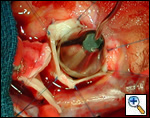

The operative approach is through a median sternotomy with the use of cardiopulmonary bypass and bicaval venous cannulation. The first dose of cold blood cardioplegia is antegrade; the remaining doses are retrograde.

High ascending aortic cannulation adjacent to the innominate artery for maximum exposure of the ascending aorta and to allow length for positioning of the patch in the ascending aorta.

One dose of antegrade cardioplegia followed by retrograde cardioplegia.

Pulmonary homograft or pericardial patches (tanned in glutaraldehyde) for the “shields”. These patches should not be too large – this will lead to aortic insufficiency.

First coronary sinus incision in noncoronary sinus to facilitate exposure of the incisions into the coronary orifice sinuses.

In most cases, the right coronary artery sinus should be opened to the left of the coronary orifice and the left coronary artery sinus to the right of the coronary orifice. Occasionally one may not have enough room between a coronary orifice and the aortic valve; in this case the incision site should be tailored to the situation.

Ensure similar orifice sizes between the proximal and distal ascending aorta after patch augmentation by the use of a sizing dilator.

Transesophageal echocardiography to assess completeness of repair, coronary blood flow postoperatively, wall motion abnormalities, and adequacy of aortic valve.